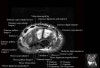

- Coronal section

Coronal T1 imaging evaluates bone marrow signal (ex. increased in avascular necrosis) and the relationship of the osseous structures to each other (ex. scapholunate disassociation).